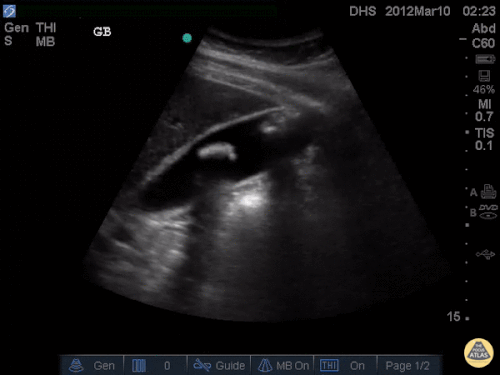

Patient with RUQ pain after eating. You place the probe on the RUQ and see this. Diagnosis ?

What is cholelithiasis

Name the sign

What is WES (wall echoing shadow sign)

What is the earliest sonographic finding of this pathology?

What sonographic finding is appreciated in the image?

In the proper clinical setting with a symptomatic patient, what diagnosis may it suggest?

What is pericholecystic fluid

What is cholecystitis